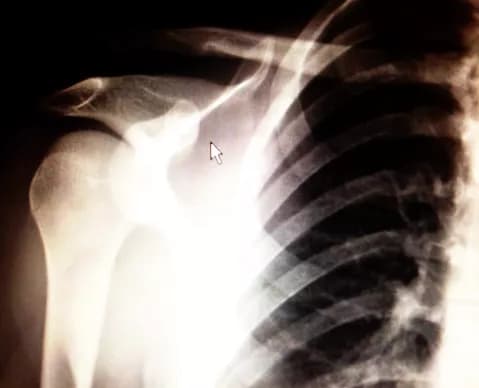

• A Dislocation occurs when the bone is forcefully moved out of its normal location in a joint

• Dislocations may involve the larger joints such as the knee and shoulder. But, it may also occur in the finger or toe joint

• Obvious deformation of the joint